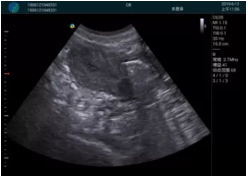

清晰顯示孕囊,通過軟件包計(jì)算孕齡7w+6d

M20實(shí)時(shí)引導(dǎo),術(shù)中清晰顯示孕囊被破壞和抽吸針的過程,清晰顯示吸引針

抽吸結(jié)束后縱切子宮,孕囊已被完全抽吸,未見明顯殘留

橫切子宮,發(fā)現(xiàn)右側(cè)宮腔靠近宮角處有少許脫模樣殘留

M20引導(dǎo)下,抽吸針找到右側(cè)宮角處再次清掃

二次抽吸后再次進(jìn)行超聲檢查,宮腔未見殘留,宮腔線清晰顯示

超聲引導(dǎo)下可視化人流是技術(shù)安全性的保障,一般對人流術(shù)設(shè)備預(yù)算不高,M20具備婦產(chǎn)科軟件包,且穿透力圖像質(zhì)量好,既滿足人流引導(dǎo)需要,也可用于床旁超聲的需求。